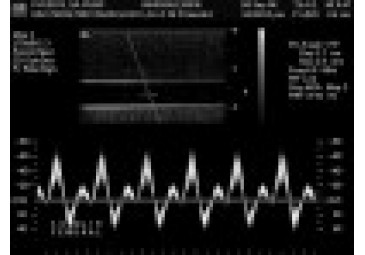

Shelley 的可編程多模態(tài) DCE 灌注模體使用基于階躍函數(shù)或典型臨床動(dòng)脈輸入函數(shù) (AIF) 輸入的壓力控制流體交換來模擬體外血流和兩室對(duì)比流藥代動(dòng)力學(xué)。

Shelley 的可編程多模態(tài) DCE 灌注模體使用基于階躍函數(shù)或典型臨床動(dòng)脈輸入函數(shù) (AIF) 輸入的壓力控制流體交換來模擬體外血流和兩室對(duì)比流藥代動(dòng)力學(xué)。這種新穎的模型產(chǎn)生了廣泛的可預(yù)測(cè)、可再現(xiàn)和可量化的時(shí)間濃度曲線 (TCC),它產(chǎn)生了模擬臨床相關(guān)灌注 TCC 的廣泛的現(xiàn)實(shí)輸入和輸出函數(shù)。該模型生成具有真實(shí)流量的 DCE 質(zhì)量保證協(xié)議的能力為驗(yàn)證灌注和動(dòng)力學(xué)建模提供了一個(gè)ji好的框架,并使 DCE 成像能夠用作比較成像掃描儀的定量成像工具。

可選泵:CompuFlow 1000 MR、CompuFlow 1000

可選泵:CompuFlow 1000 MR、CompuFlow 1000 或雪萊推薦的蠕動(dòng)泵。